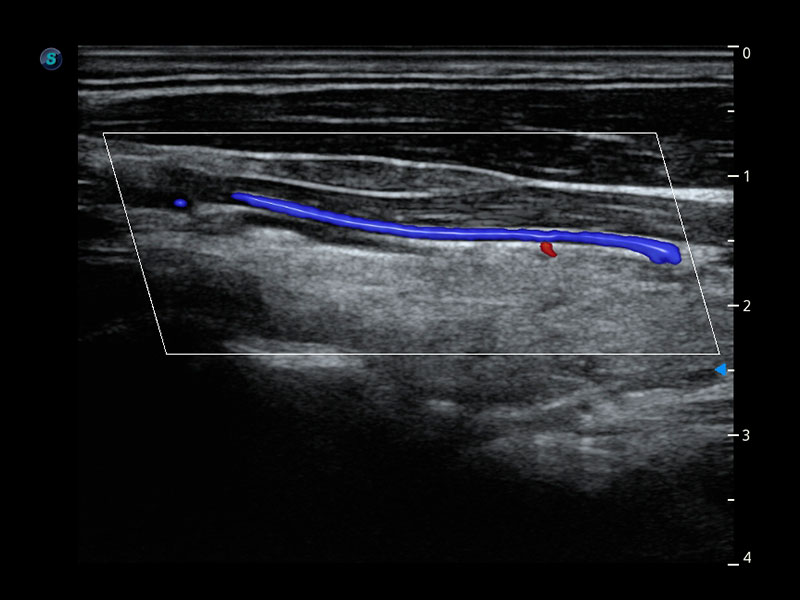

Micro F

Consente la visualizzazione delle strutture microvascolarizzate

Micro F offre un metodo innovativo per ampliare la portata di flusso visibile nell'ecografia, in particolare per visualizzare l'emodinamica dei piccoli vasi a flusso lento. Grazie all'adozione di un filtro adattivo avanzato e all'accumulo di segnali temporali e spaziali, Micro F è in grado di distinguere in modo efficace il flusso minuto dal movimento di tessuto sovrapposto e di rappresentare l'emodinamica con sensibilità e risoluzione spaziale più elevate.

• Arteria pericallosa fetale con Micro F

• Flusso ematico renale con Micro F

• Nodulo tiroideo con Micro F

• Linfonodo cervicale con Micro F